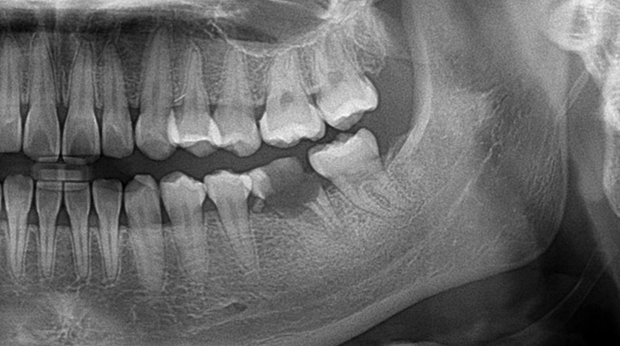

매복 사랑니 발치

고난도 수술 진료

임플란트와 사랑니 발치는 외과적 시술로 잇몸을 절개하는 외과적 시술은

짧으면 짧을 수록 시술 후 붓기와 통증이 최소화됩니다.

치과의사 경력 14년차 구강외과 전문의가 빠르고 안전하게, 아프지 않게 수술해 드립니다.

치과경력 14년차 구강외과 전문의

연세대학교 치과대학 구강외과 임상 조교수